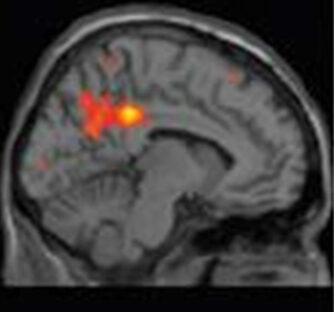

Test de pénétration de médicaments dans le cerveau par imagerie TEP